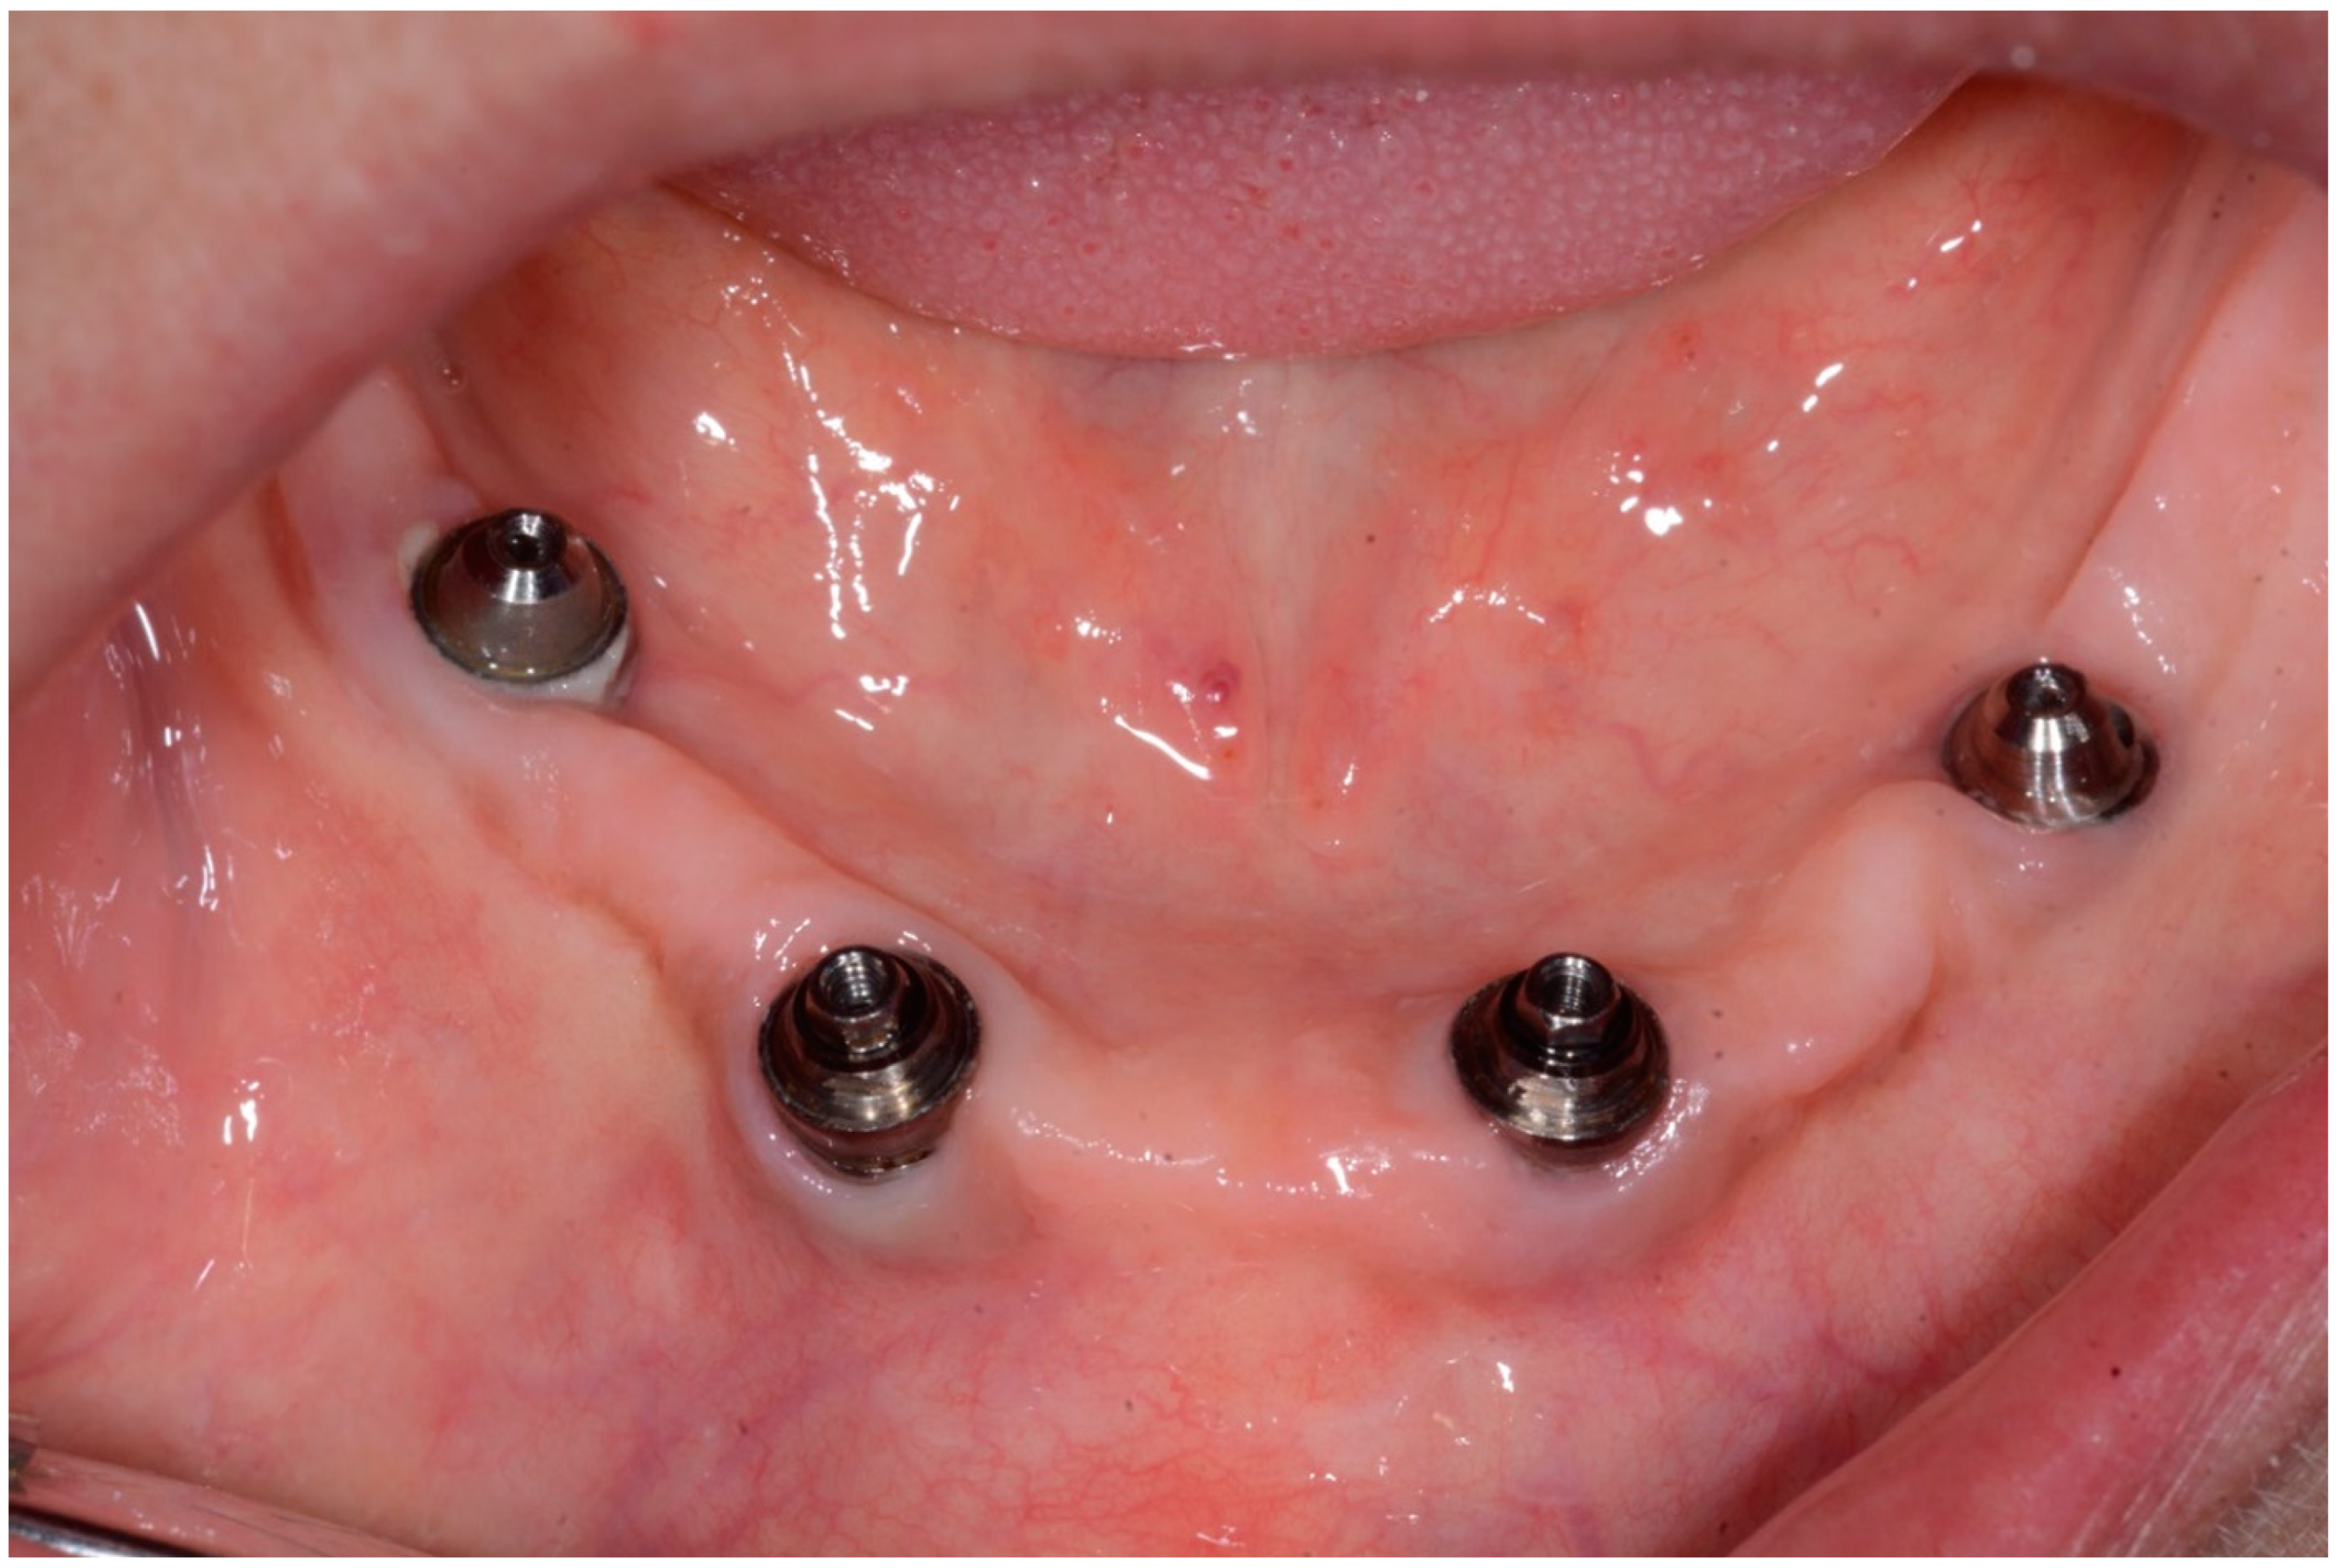

Figure 12.

Condition of peri-implant tissues in patient in 6 months after treatment.

Bidimensional radiographic assessment of the lower jaw implants (with periapical and panoramic radiograph) was done. In the lower jaw, a concave bone resorption of about 2.5 mm mesial and distal to both distal implants were observed, and there was no bone resorption in two central implants (Figure 13 and Figure 14).